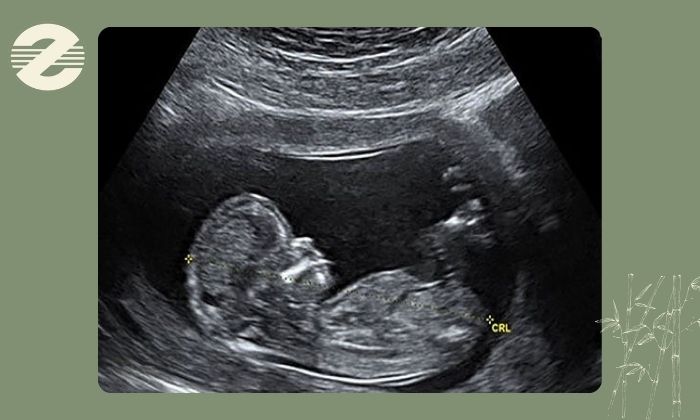

سونوگرافی تشخیصی در دوران بارداری بر پایه امواج صوتی با فرکانس بالا انجام میشود. این امواج پس از ورود به بدن به بافتهای مختلف برخورد کرده و بازتاب آنها توسط دستگاه تحلیل میشود تا تصویری دقیق از وضعیت جنین، جفت و میزان مایع آمنیوتیک ایجاد گردد.

نکته بسیار مهم این است که در سونوگرافی از اشعه یونیزان استفاده نمیشود؛ به همین دلیل برخلاف روشهایی مانند رادیوگرافی یا سیتیاسکن خطرات ناشی از تابش اشعه برای مادر و جنین وجود ندارد.

به همین علت سونوگرافی یکی از ایمنترین و پرکاربردترین روشهای تصویربرداری در دوران بارداری به شمار میرود و سالهاست که در سراسر جهان تحت نظارت نهادهای علمی معتبر مورد استفاده قرار میگیرد. تاکنون شواهد علمی معتبری مبنی بر آسیبزایی برای جنین گزارش نشده است. البته مانند هر اقدام پزشکی دیگر انجام آن باید با اندیکاسیون مشخص، در زمان مناسب و توسط افراد متخصص صورت گیرد تا ضمن حفظ کیفیت تشخیص، اصل ایمنی جنین نیز بهطور کامل رعایت شود.